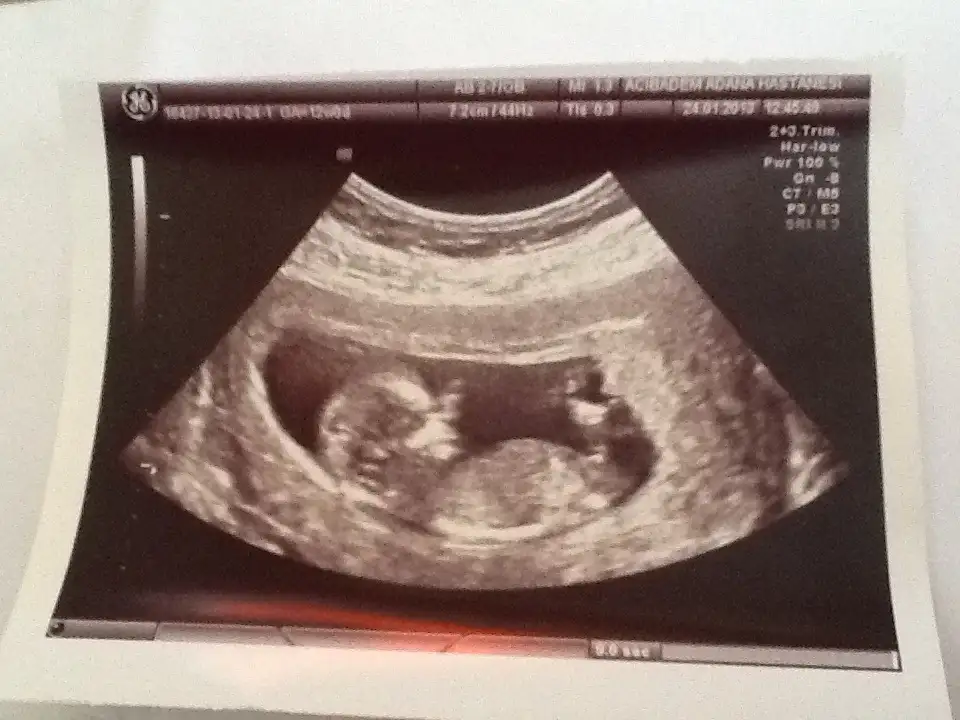

ama ikinci bebegin gercekten dik nubu var suankinin yani

Tekrar düzgün yüklüyorum girersen bakarsın canım. Bu arada bu ultrason görüntüsünü verdiğinde Dr. Erkek gibi filan dedi ama kesin değil dedi 2 hafta sonra kontrolde söylerim dedi

aslında bende az buçuk anladığım kadarıyla ki konu sahibi daha doğrusunu o seyleyecektir galiba benim gördüğüm kızlerın paralel durmaları kadar biraz daha vücudun aşağısında ama erkek çocukların daha yukarıda duruyorlar tabi bu benim gözlemlediğim yanlışta söylüyor olabilirim doğrusunu orkdm söyleyecektir, bende bebeğimin ultrasonda izlerken okada hareketliydiki yerinde duramıyordu:)) ama dikkat ettiğim kızlarınkinden çok erkek nubları gibiydi tabi duruşu bebeğinde etkili oluyor benimkisi çok hareketliydi kurban olduğum artık kız erkek neye döner bilmem..